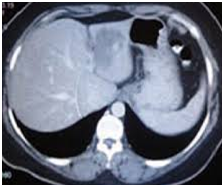

Blood investigations revealed anemia (Hb 7gm/dl), normal total and differential leukocyte count and severe thrombocytopenia (platelet count 70,000/μL), AST 200, ALT 450, ALK 678, GGT 150, T. Billi 10 mg/dl, D 6mg/dl, PT 16 sec, PTT 30sec, INR 2U/A-U/C were normal. Other biochemistry lab test was normal. TORCH study, viral marker hepatitis, TFT, B/C and metabolic study were normal. HIDA scan was normal. Chest X ray was normal. Brain and pelvic CT were normal. In sonography typically well-defined hyperechoic lesions was seen in left lobe. So contrast abdominal spiral CT was done and in CT well defined enhance lesion was seen due to liver hemangioma (Figure 1). So surgical consult was done then the infant transfer to surgery ward and the left lobe of liver was lobectomy and after 2 weeks the T. Billi 3D1 and after 2 months the infant was good and lab test were normal.

Figure 1 CT well defined enhance lesion was seen due to liver hemangioma.